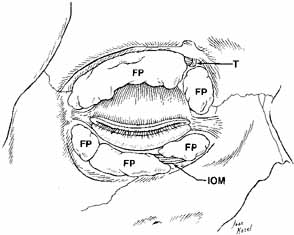

Fig. 14 Anterior view of deep dissection of orbital fat-pads to show trochlea

dividing fat-pads in the upper eyelid. The inferior oblique

muscle divides the medial from the central fat, and the arcuate expansion

fascia of the inferior oblique divides the central from the lateral

fat pads in the lower eyelid. (FP, fat pad; T, trochlea; IOM, inferior oblique muscle) Fig. 14 Anterior view of deep dissection of orbital fat-pads to show trochlea

dividing fat-pads in the upper eyelid. The inferior oblique

muscle divides the medial from the central fat, and the arcuate expansion

fascia of the inferior oblique divides the central from the lateral

fat pads in the lower eyelid. (FP, fat pad; T, trochlea; IOM, inferior oblique muscle)